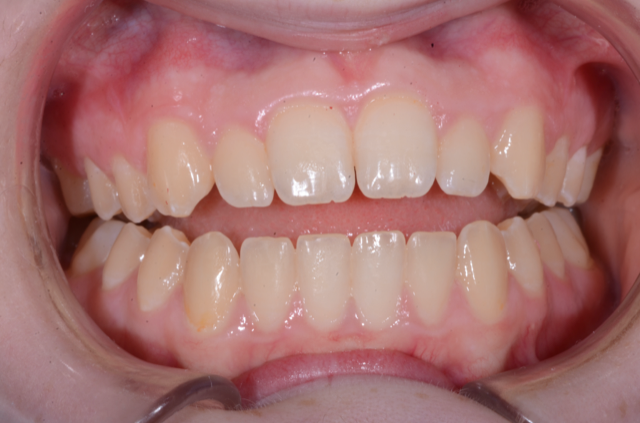

- How to assess health and dysfunction of the somatognathic system

- The relationship of the compromised airway to the compromised joint and occlusion patient